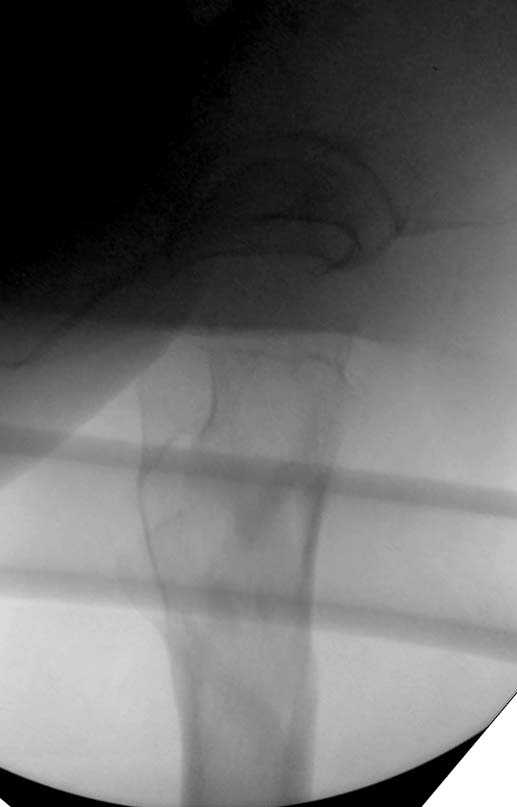

Здесь представлен случай, где в послеоперационном периоде обнаружена техническая ошибка, Gamma 3 установлен с нарушением методики. Больная в 91 лет, прооперирована через день после поступления и выписана через 48 часов.

При первом послеоперационном поликлиническом осмотре больная предъявила жалобы на боли в бедре. В серийных снимках обнаружен продольный перелом верхнего отдела бедра.

Считаем, что техническая ошибка произошла во время установки гвоздя, когда рассверливанию канала не уделили должного внимания. Канал остался узковат, и гвоздь был забит с силой. Полная нагрузка конечности приостановлена на две недели, и боли в конечности изчезли. Больная начала нагрузку и перелом срастается.-- Djoldas Kuldjanov, M.D.Associate ProfessorDepartment of Orthopedic SurgerySt. Louis University

I have a different interpretation of this case. I suspect you did not tighten the set screw all the way in order to allow sliding of the lag screw and fracture fragment compression, as you would for a standard intertrochanteric hip fracture. This is a reverse obliquity fracture, so the result is migration of the proximal segment. I doubt reaming the canal would have prevented this. Had the set screw been fully tightened, there would be no postoperative fragment motion.

I looked at the films again and saw that you are referring to the nondisplaced shaft fracture, not the proximal fragment position. Sorry.